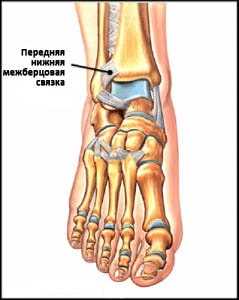

Передняя нижняя межберцовая связка (далее ПНМС), отвечающая за стабилизацию U-образной «вилки» берцовых костей, подвергается травмированию в случае ротации зафиксированной на той или иной поверхности стопы. Зачастую, образующийся после заживления данного вида связки рубец, может спровоцировать развитие импинджмента.

Рис. 5 Анатомия ПНМС